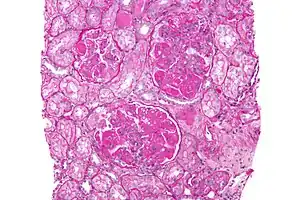

In DPGN Most of the glomeruli show endothelial and mesangial proliferation, affecting the entire glomerulus, leading to diffuse hypercellularity of the glomeruli, producing in some cases epithelial crescents that fill Bowman's space. When extensive, immune complexes create an overall thickening of the capillary wall, resembling rigid "wire loops" on routine light microscopy. Immune complexes can be visualized by staining with fluorescent antibodies directed against immunoglobulins or complement, resulting in a granular fluorescent staining pattern. Electron microscopy reveals electron-dense subendothelial immune complexes (between endothelium and basement membrane). In due course, glomerular injury in DPGN gives rise to scarring (glomerulosclerosis). Most of SLE patients with DPGN have hematuria with moderate to severe proteinuria, hypertension, and renal insufficiency.[2]

The glomeruli are the filters in the kidneys. When working normally they will move the waste, excess electrolytes, and unnecessary fluid from the bloodstream to the urine.[8] When a person develops DPGN, over 50% of the glomeruli (diffuse) become inflamed. There is also an increase in mesangial, epithelial, and endothelial (proliferative) cells. Inflammatory cells are also rapidly developed.[9] This causes damage to the kidneys and does not allow for proper filtration.

A kidney biopsy is the most important diagnostic tool. With a biopsy, the sample will be looked at histologically. With this information, a proper diagnosis can be completed. There are many forms of glomerulonephritis, but under a microscope, DPGN will show increased cell count of polymorphonuclear cells, cellular crescents, and fibrinoid necrosis. A patient with DPGN will have more than 50% of their glomeruli involved.[4][5] If a patient has DPGN, that means they have an active form of glomerulonephritis.[10]

The percentage of glomeruli that show crescents usually correlates to the severity of the renal failure.[18][19]